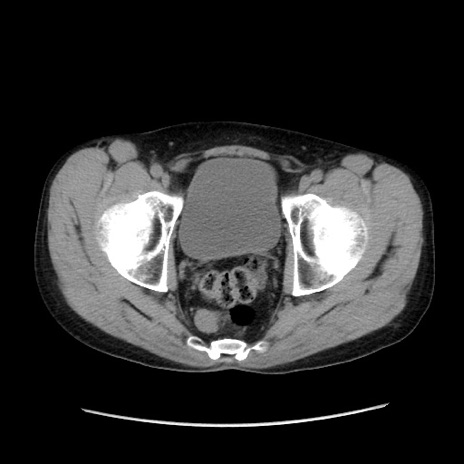

症例37(横断像)

【症例】40歳代 男性

【主訴】腹痛

【現病歴】4時間ほど前に電車に乗車中に臍部上より腹痛出現。徐々に増悪し起立困難となり、救急外来受診。生ものは数日食べていない。今朝お雑煮を食べた。

【身体所見】BT 36.8℃、BP 117/84mmHg、HR 91/min、SpO2 97%、苦悶様、腹部:臍上部広範囲圧痛あり、反跳痛±

【データ】WBC 8100、CRP 0.03